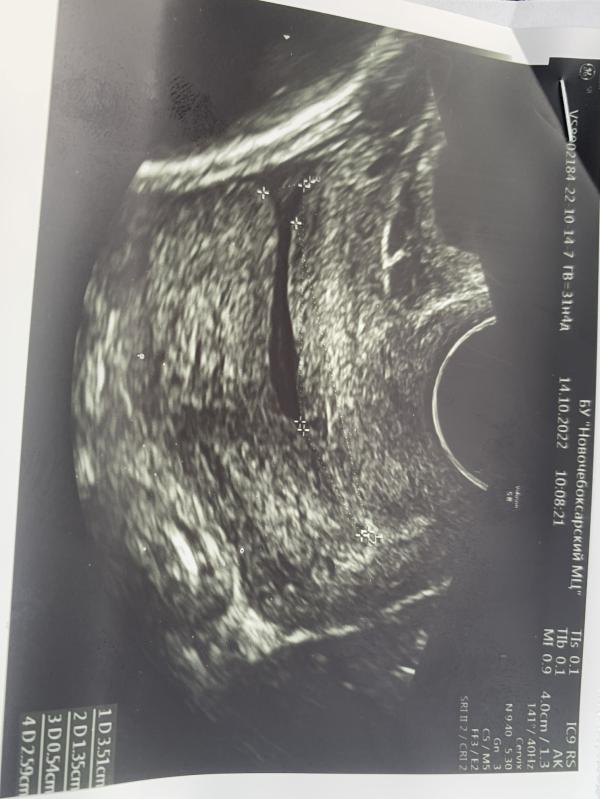

Раскрытие 5мм😱 угроза преждевременных родов🤦🏼♀️ если бы не выпросила талон на узи, так бы и не знала,тк ничего не болело.🤦🏼♀️

Вообщем положили на сохранение, надеюсь все будет хорошо